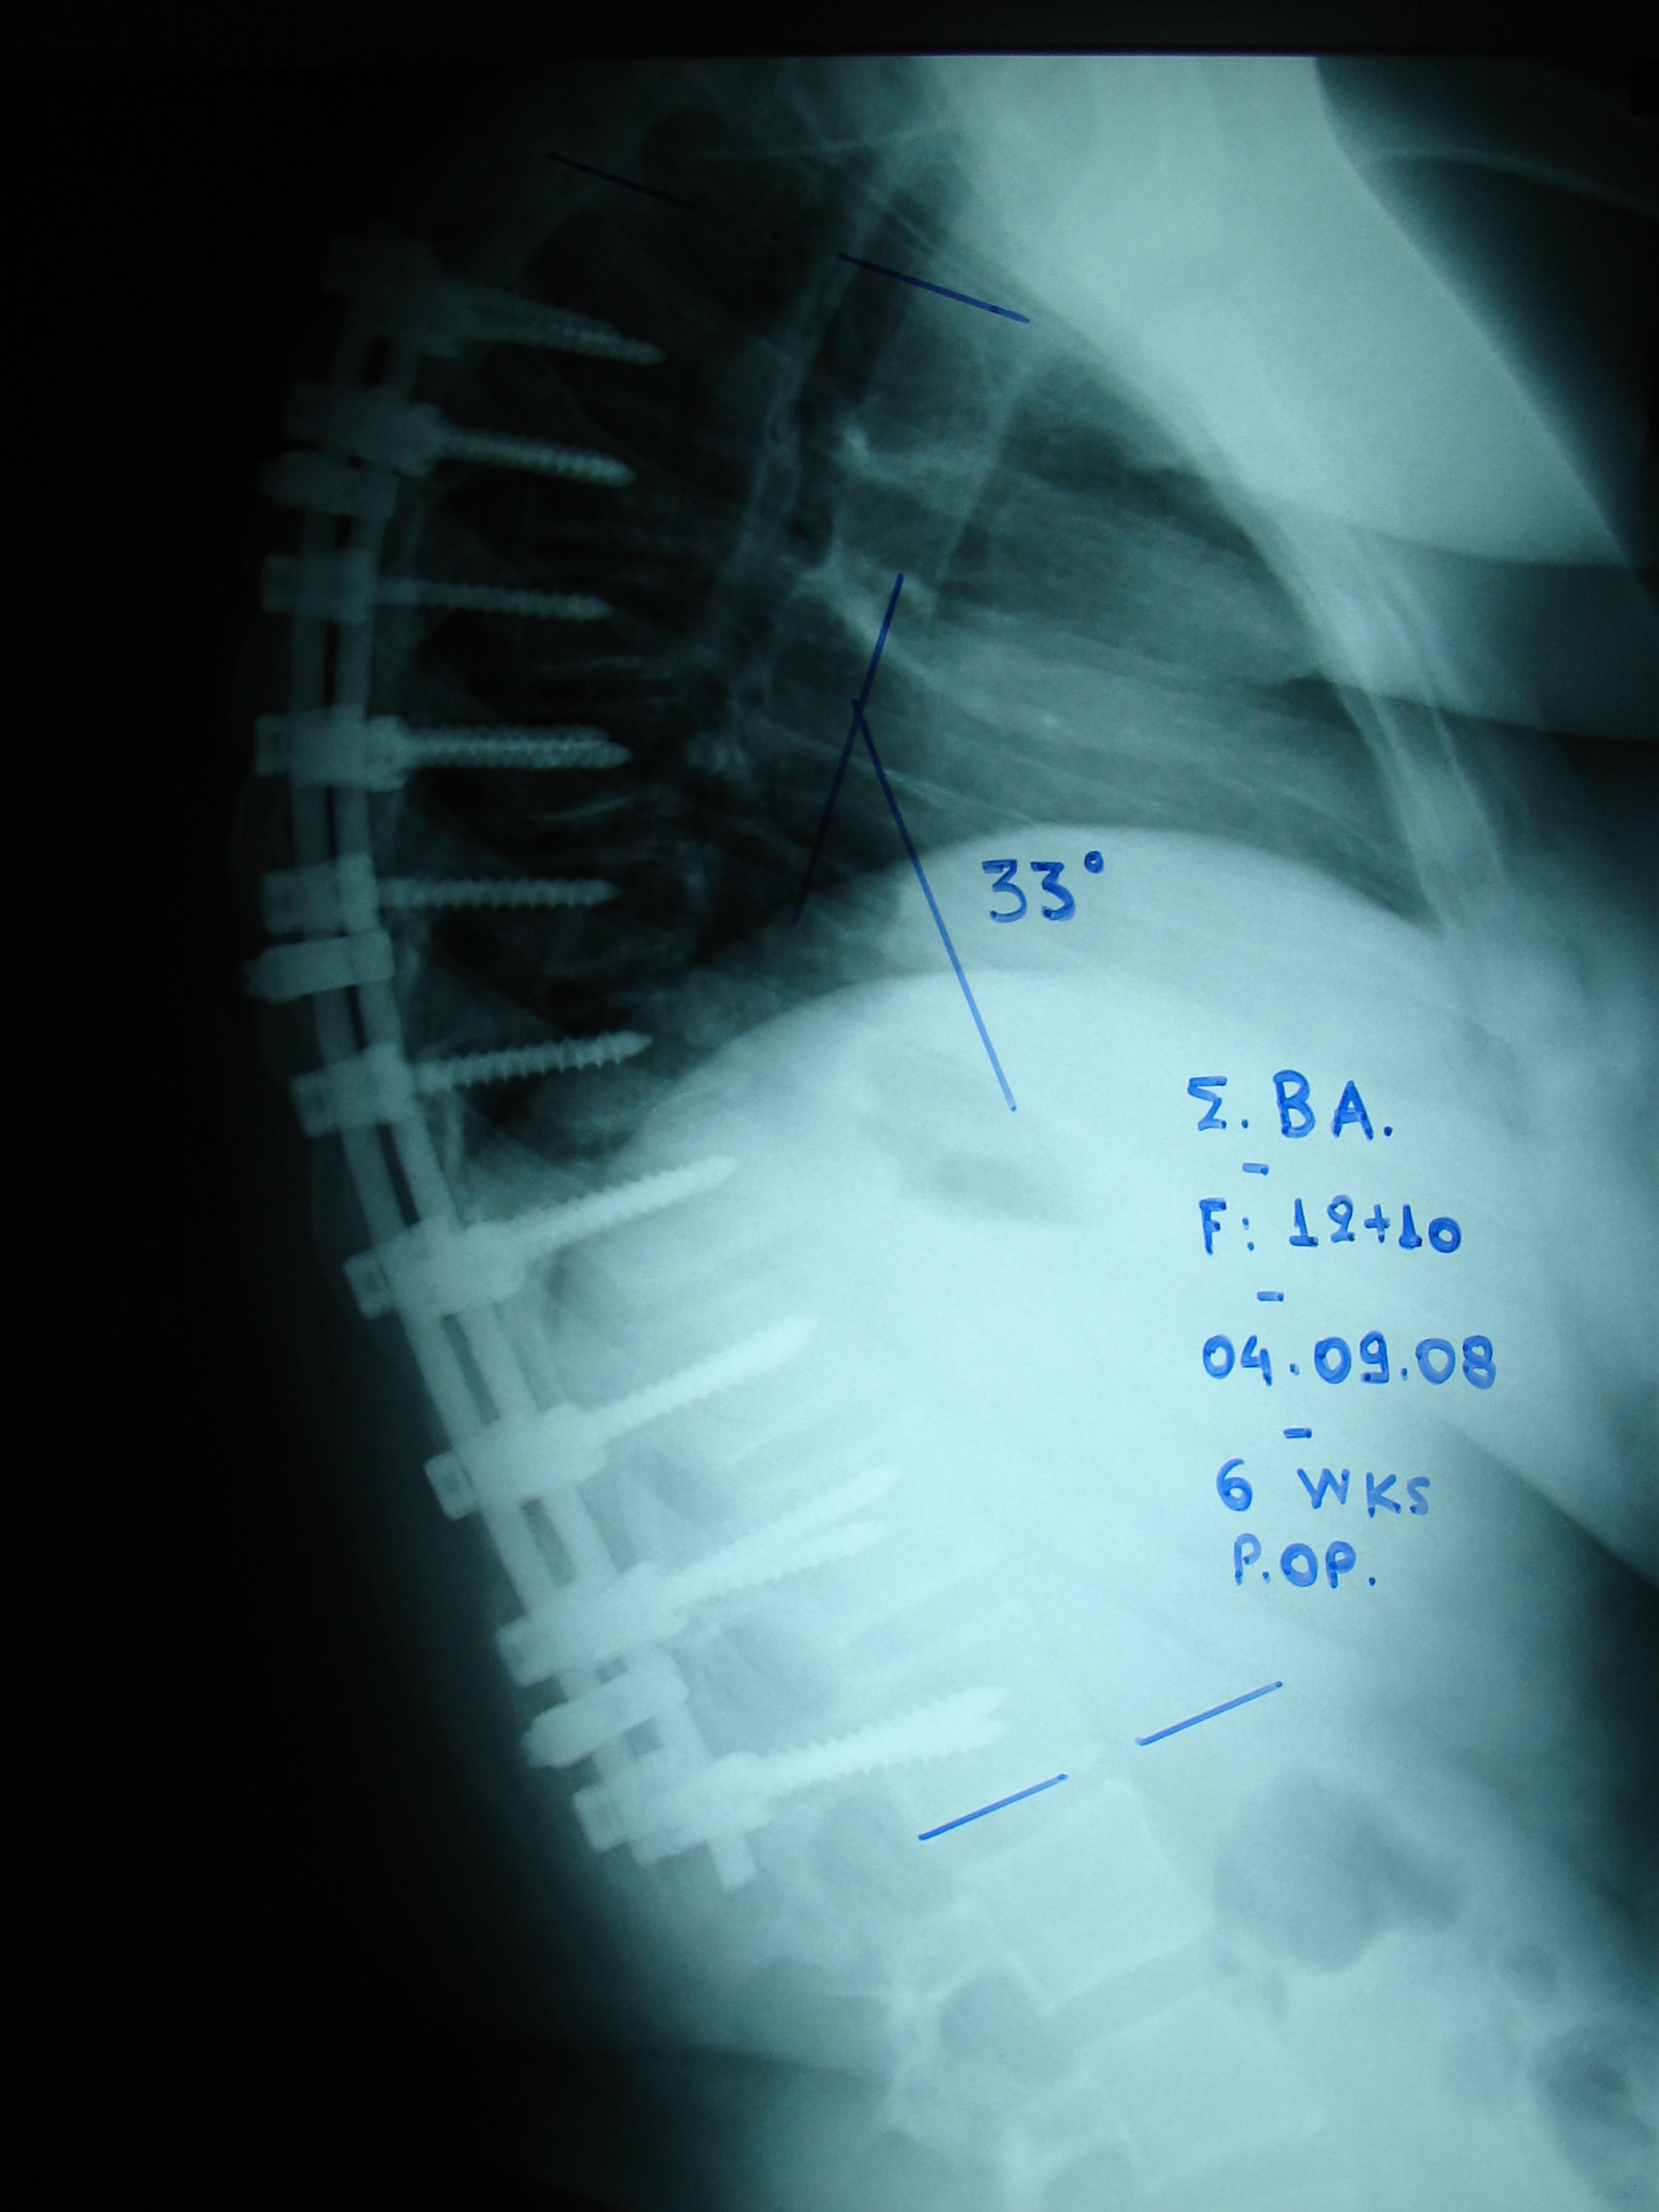

Εικόνα 2: Μεταγχειρητικές ακτινογραφίες (6 εβδομάδες μετά τη χ.ε.)

Είναι εμφανής η εντυπωσιακή διόρθωση της κυφωτικής παραμόρφωσης. Οι μετρήσεις δείχνουν ότι η κύρτωση της σπονδυλικής στήλης είναι εντός των φυσιολογικών πλαισίων.